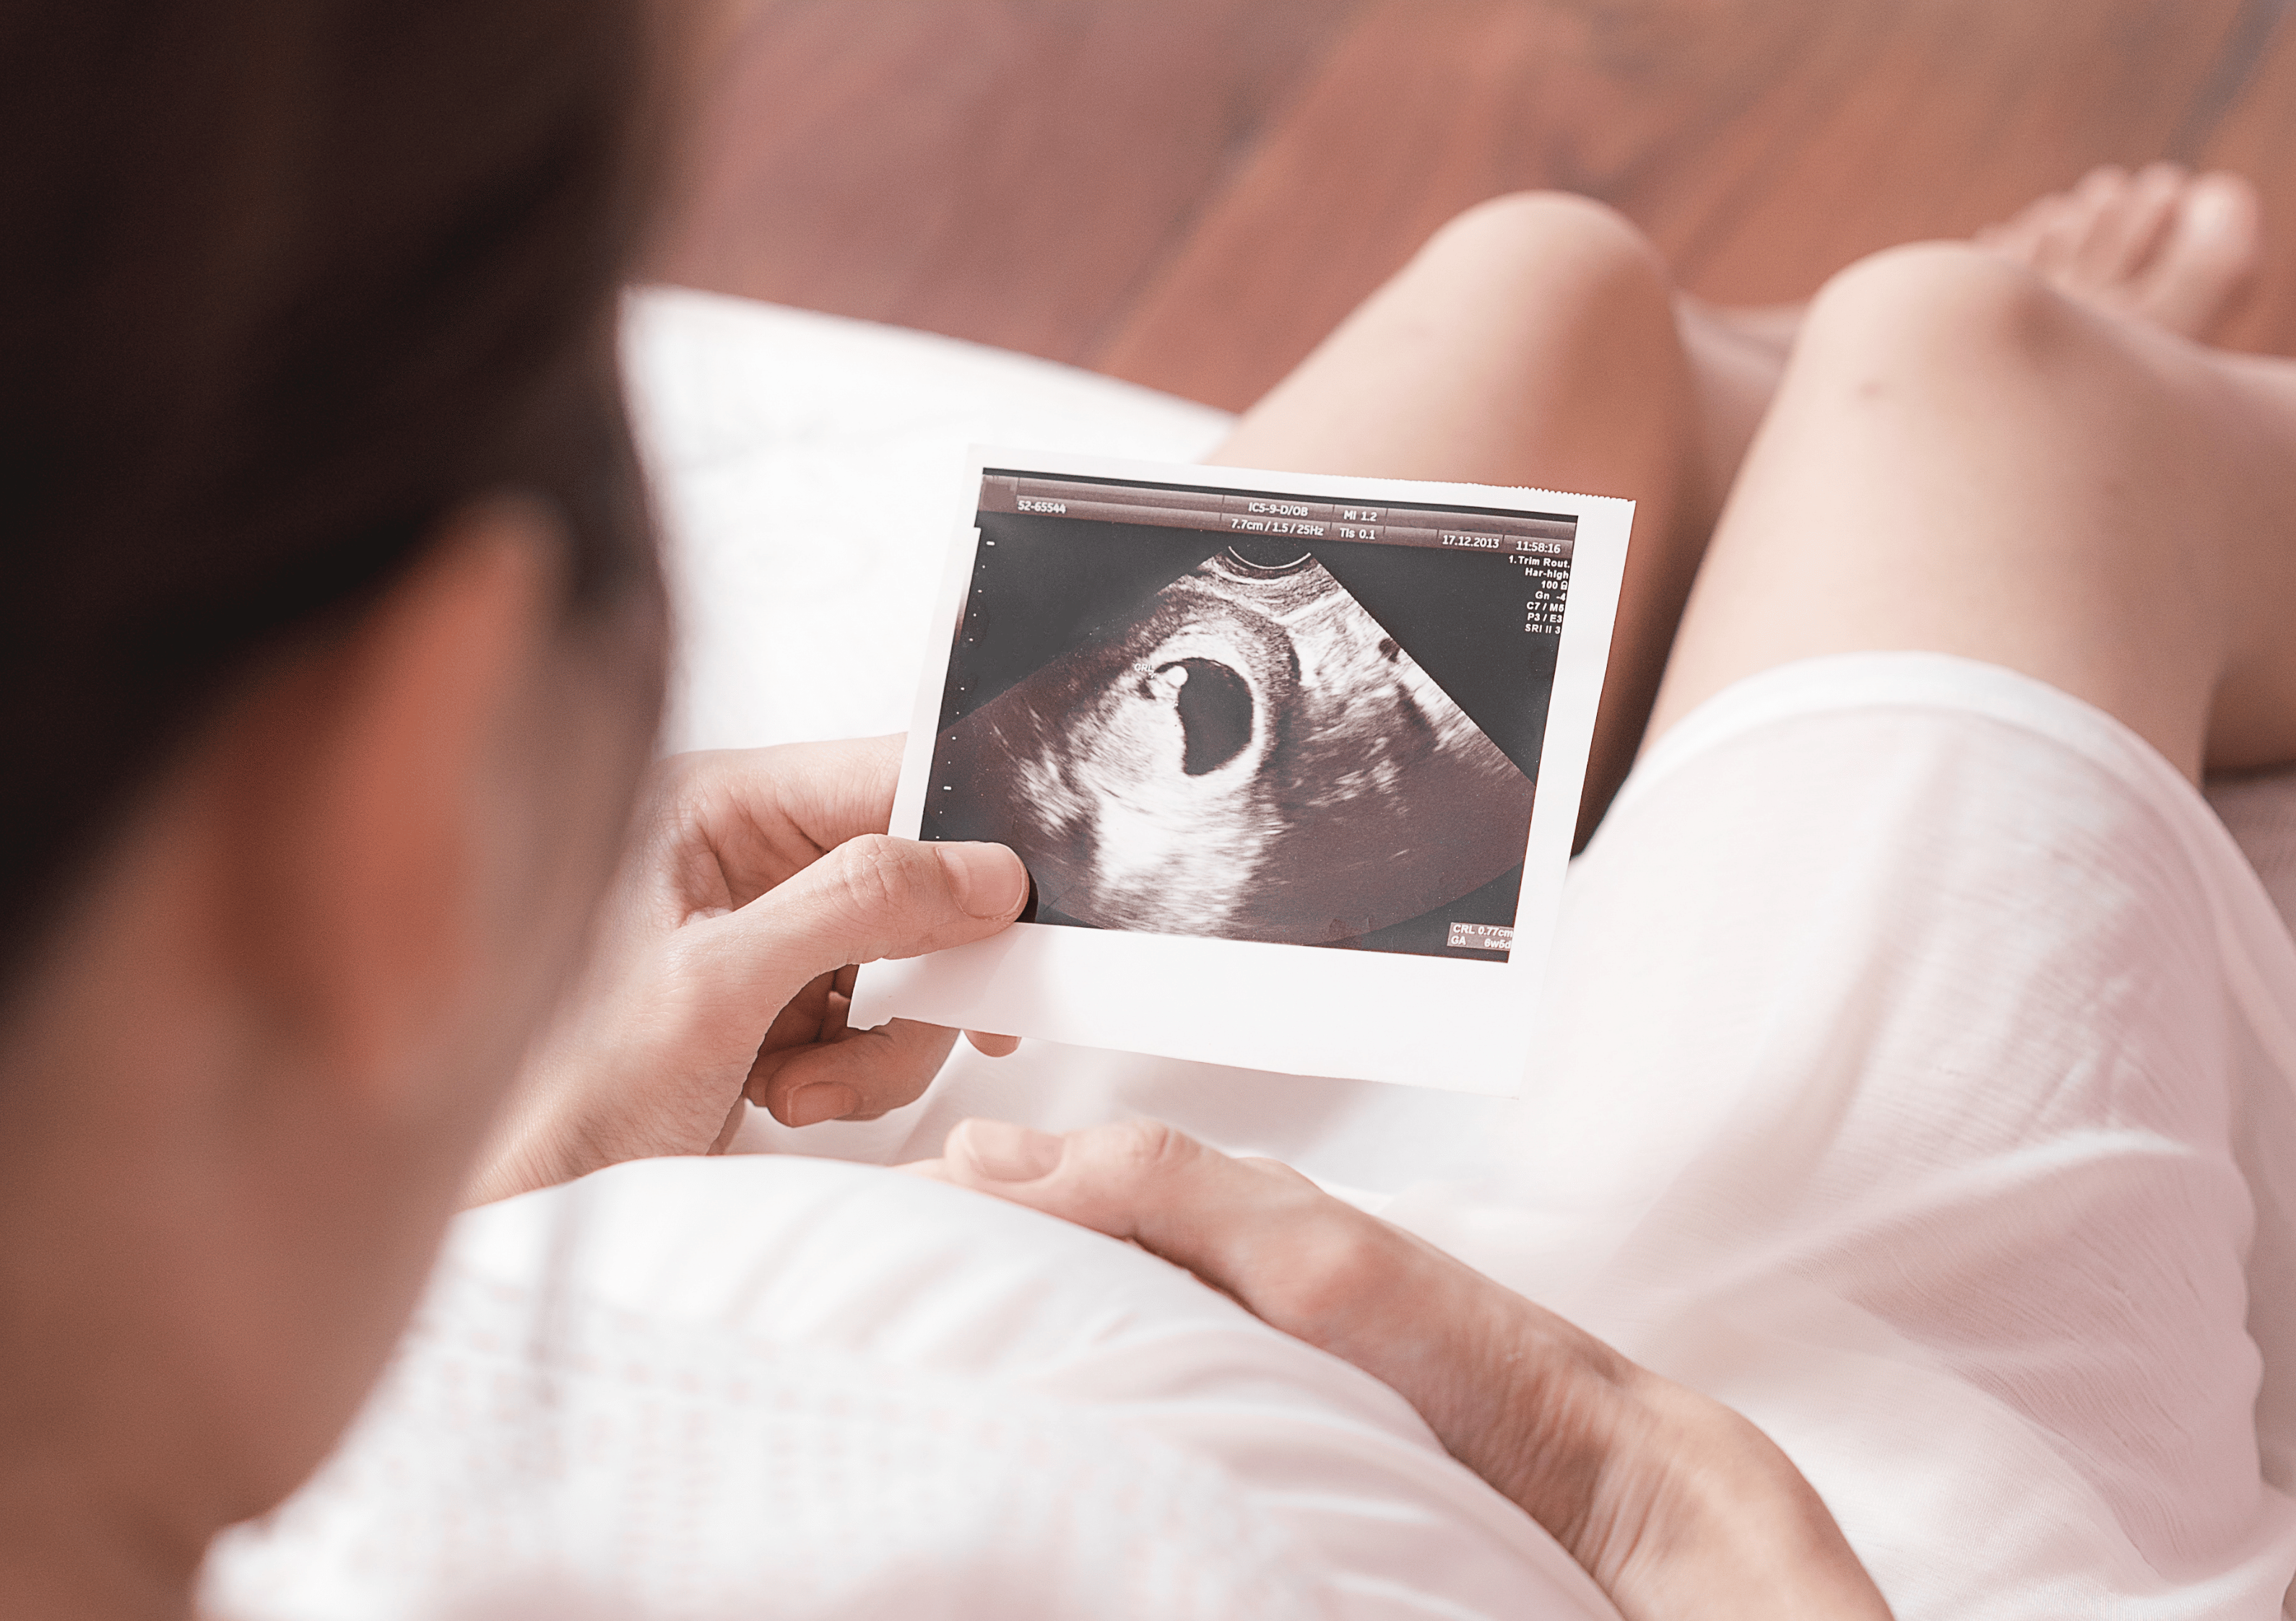

Optimiere deine Ernährung während der Schwangerschaft, um deinen Körper bestmöglich auf die Geburt vorzubereiten. Mit nährstoffreichen Lebensmitteln kannst du die Energie steigern, Beschwerden lindern und die Geburt erleichtern.

Bereite deinen Körper mit der richtigen Ernährung optimal auf eine Schwangerschaft vor. Entdecke, wie du deine Fruchtbarkeit unterstützen und deinem Wunsch nach einem Baby ein Stück näher kommen kannst.